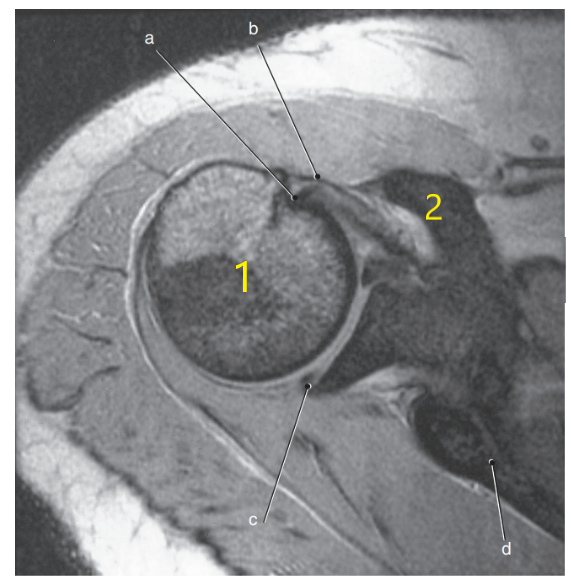

What is letter a?

Biceps brachii tendon

What is letter b ?

Supraspinatus muscle

What is letter c ?

Posterior glenoid labrum